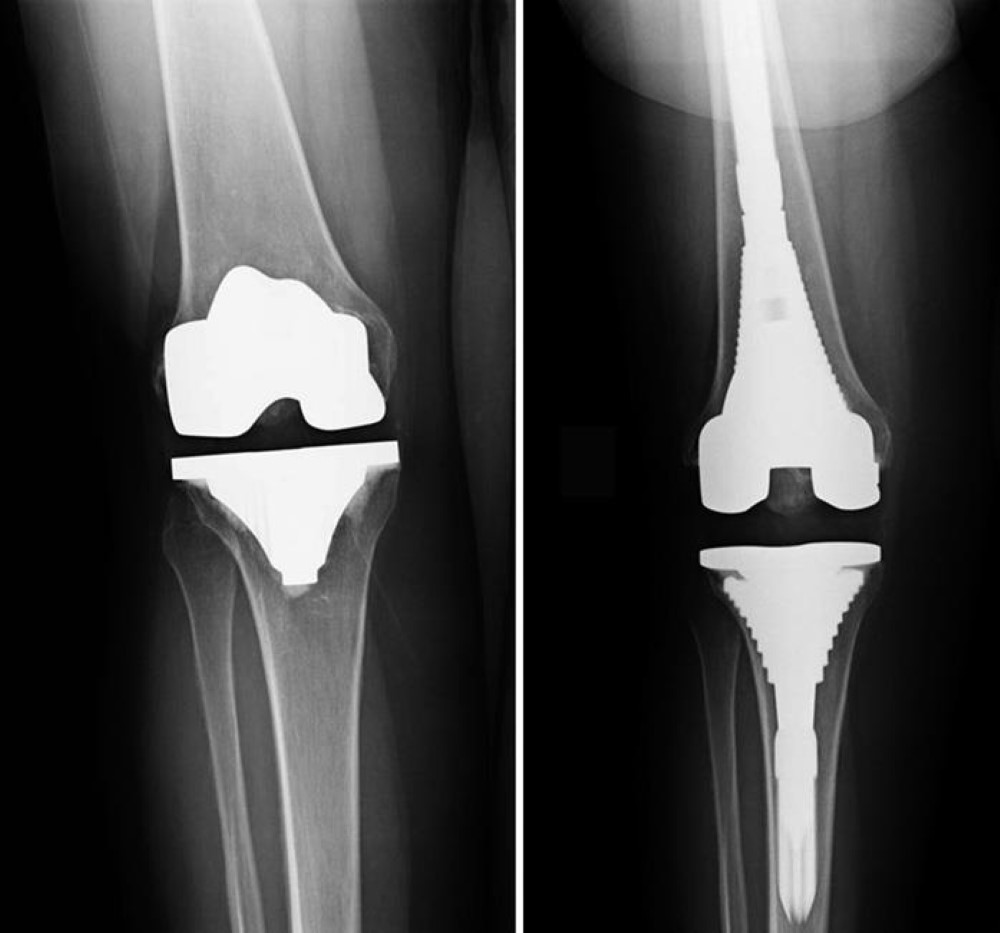

x-ray of loose knee implant and revision components

(Left) In this X-ray, the primary knee replacement implant is unstable due to weakened bone. (Right) In revision surgery, components with longer stems fit more securely into the bones and provide stability.

Reproduced from Daines BK, Dennis DA: Management of Bone Defects in Revision Total Knee Arthroplasty. Instr Course Lect 2013; 62:341-348.